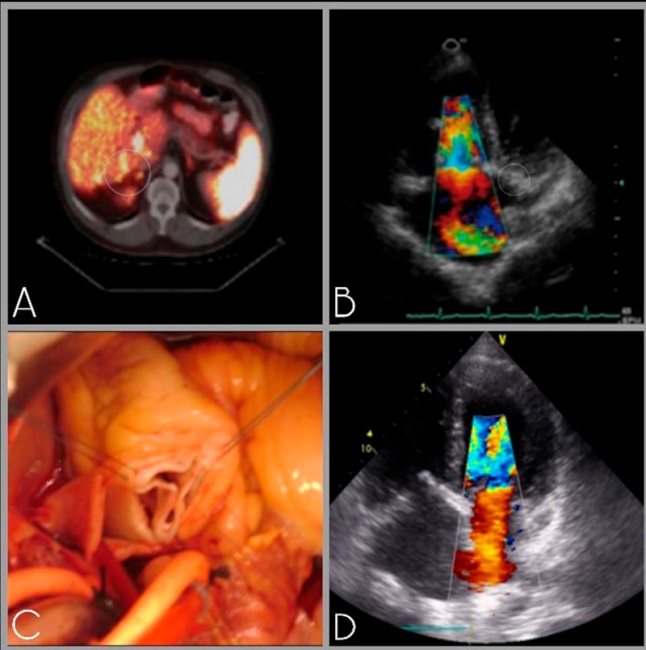

Paciente de sexo masculino de 50 años con antecedentes de hipertensión arterial, dislipemia y tabaquismo. Como antecedente oncológico fue sometido a una resección pancreática de un tumor carcinoide y ablación por radiofrecuencia de metástasis hepáticas 6 años antes de presentar sintomatología cardíaca (Imagen 2 A). En esta ocasión consulta por disnea progresiva y sintomatología de insuficiencia cardíaca derecha. En el ecocardiograma Doppler se evidencia insuficiencia tricúspidea grave asociada a insuficiencia pulmonar moderada con signos de sobrecarga ventricular derecha, presión pulmonar sistólica de 45mmHg y excursión sistólica del plano del anillo tricuspídeo (TAPSE) conservada (Imagen 2 B).

Se decide resolución quirúrgica mediante el doble reemplazo tricúspideo y pulmonar con prótesis biológicas (N31 y N27 respectivamente) y profilaxis intraoperatoria con octreotide (Imagen 2 C). El paciente evoluciona de forma favorable sin complicaciones, siendo egresado de la institución al 6to día postoperatorio.

A los 4 años de la intervención, vuelve a evolucionar con disnea progresiva y se diagnostica progresión de la enfermedad carcinoide con afectación de válvula mitral. En el ecocardiograma Doppler se evidencia válvula mitral con retracción valvar e insuficiencia mitral grave por falta de coaptación, con orificio regurgitante efectivo (ORE) 0,5 (Imagen 2 D). La prótesis tricúspidea y pulmonares se encuentran normofuncionantes con gradientes adecuados. El paciente es intervenido nuevamente y se realiza reemplazo mitral biológico con válvula N29 con buena evolución postoperatoria y alta al décimo día.